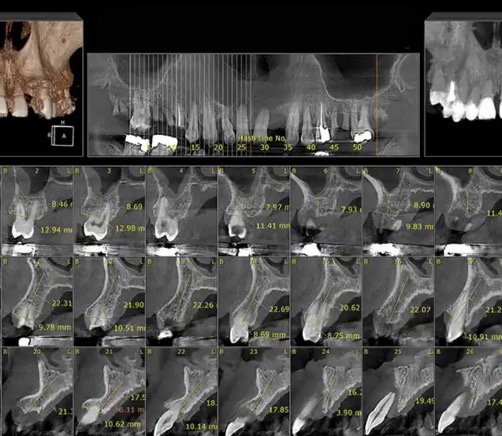

مرحله دوم: انجام عکس رادیوگرافی و سی تی اسکن مخصوص (C.B.C.T)

سپس تایید انجام ایمپلنت با توجه به اسکن، استخوان فک، سینوس ها، اعصاب و شرایط کلی بیمار